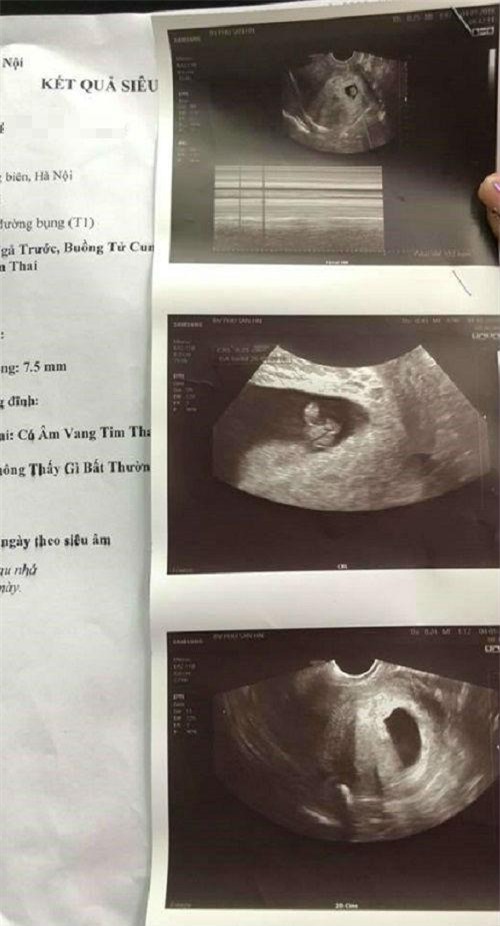

Kết luận của bác sĩ BV Đa khoa Đức Giang.